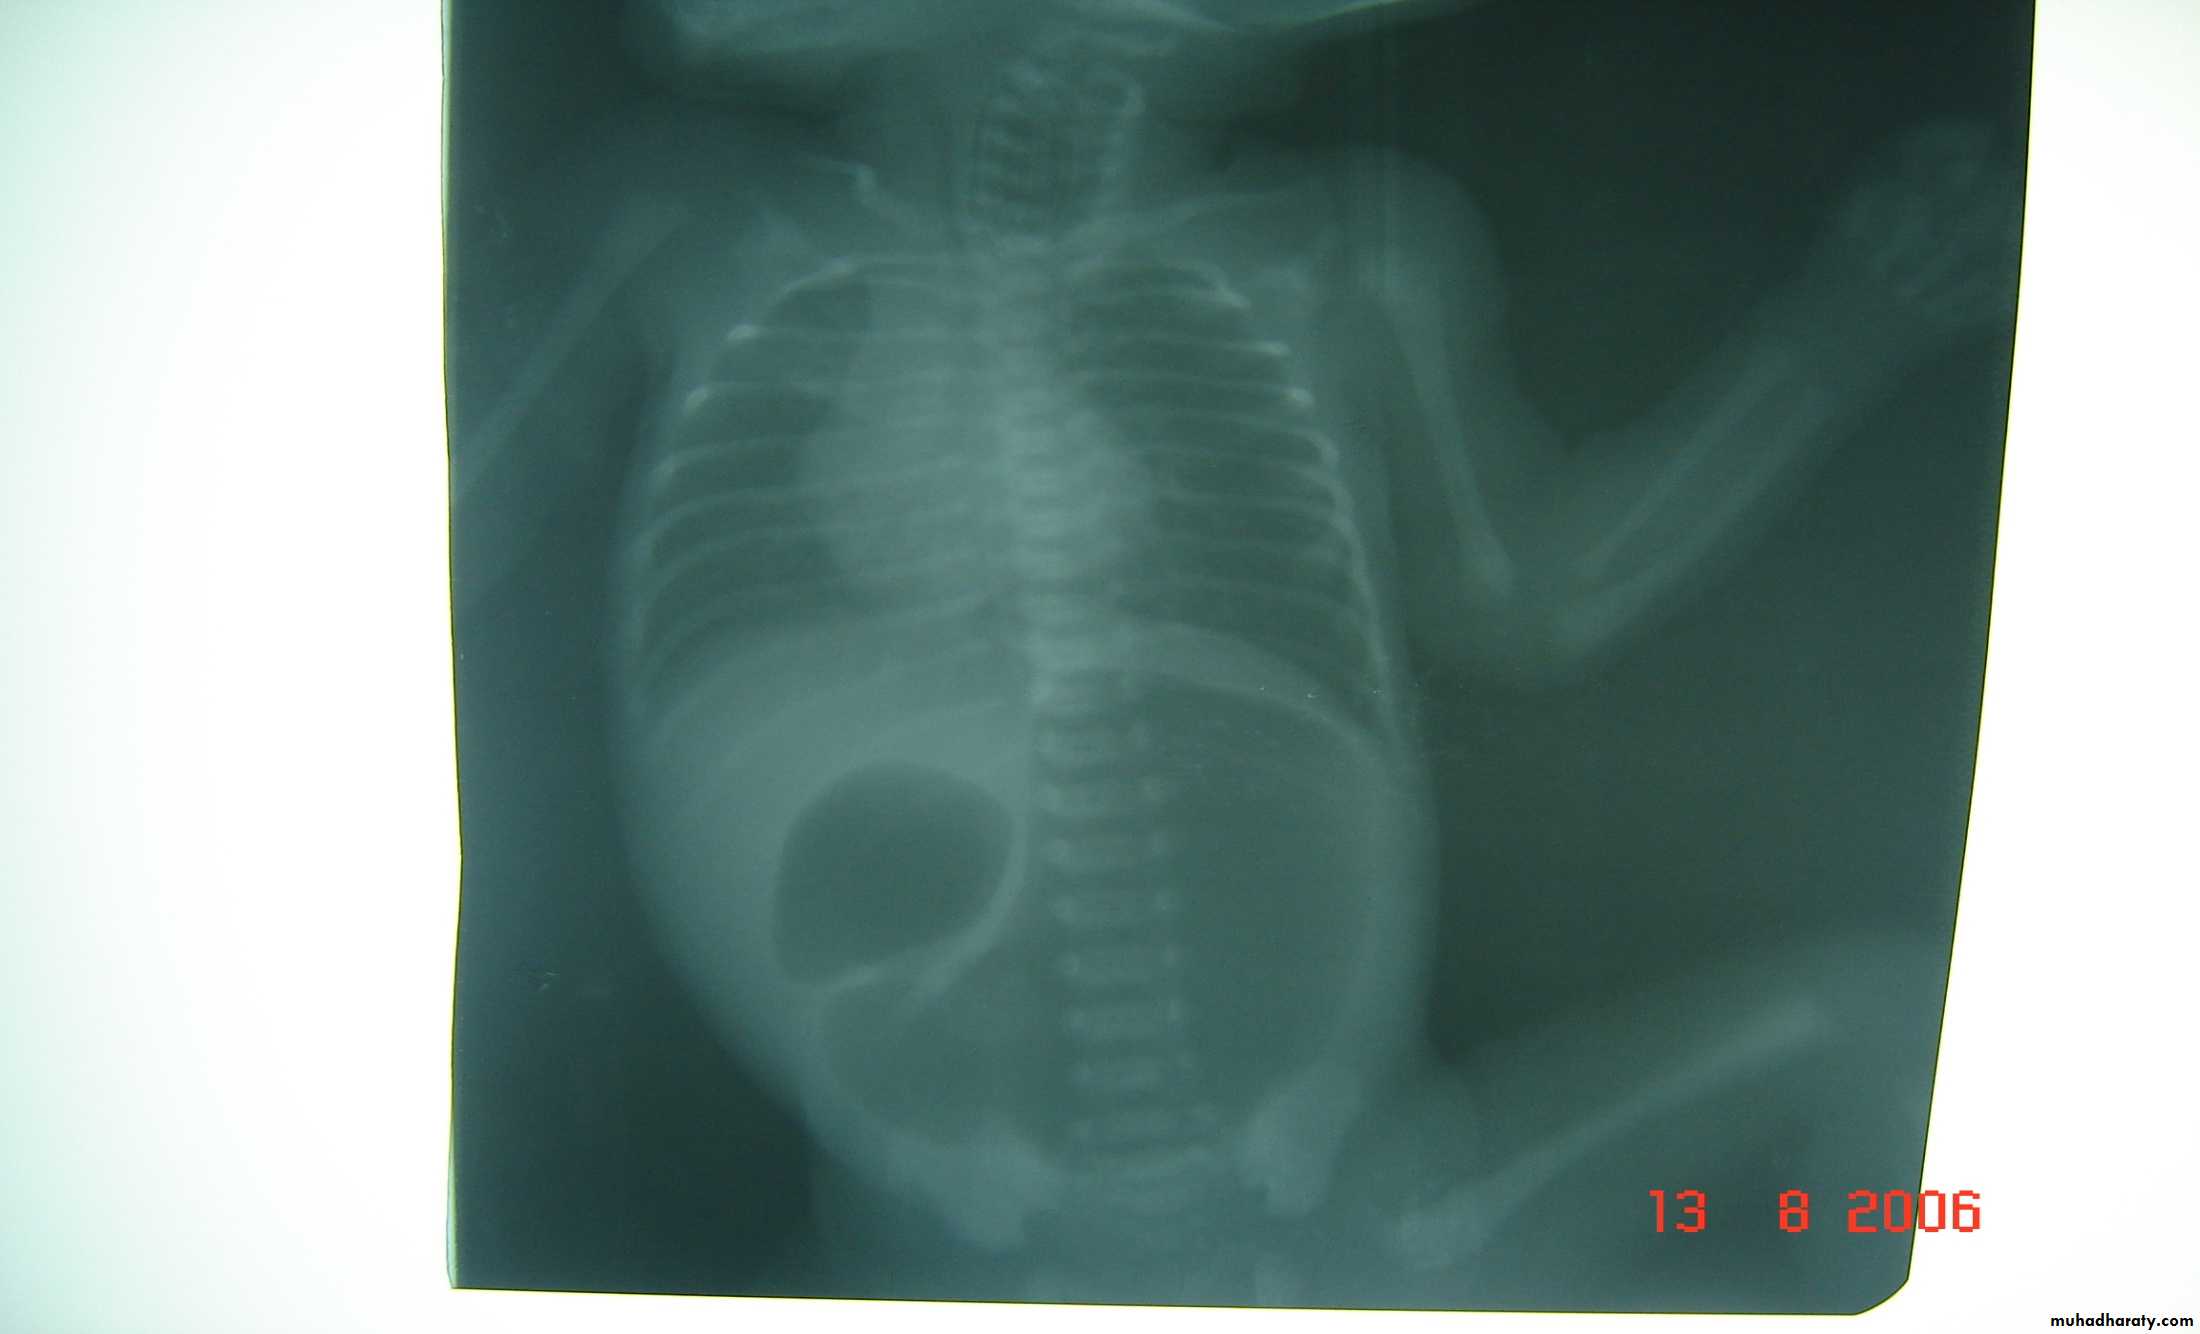

Meconium ileus+atresia